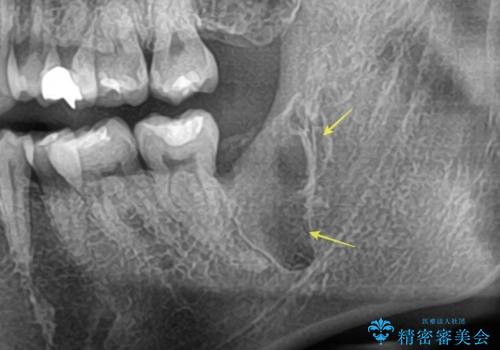

【埋伏智歯と埋伏智歯の過剰歯の抜歯】埋まっている親知らず2本の抜歯

担当医 河野豊嘉